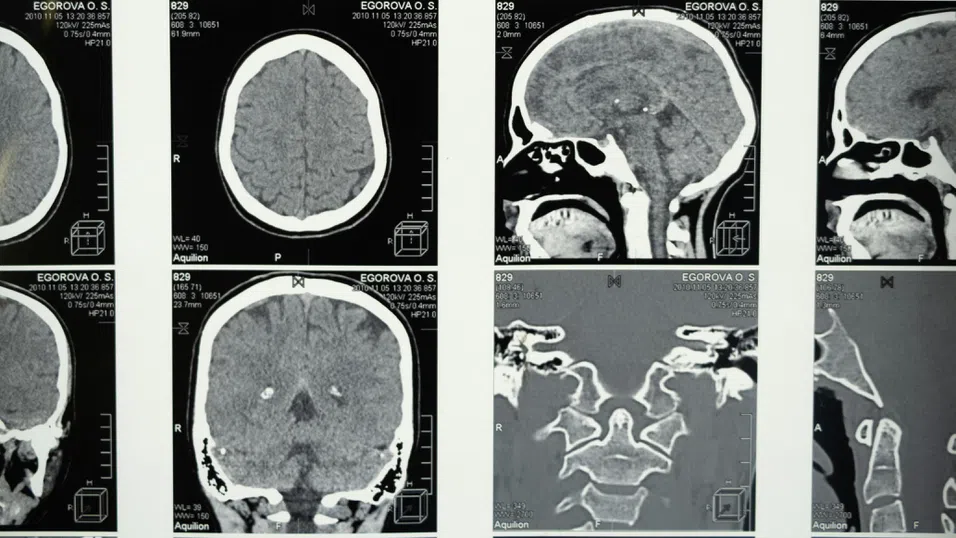

Лекари определят като „изключително окуражаващи“ резултатите от ново проучване, което показва, че тройна „смарт“ инжекция може да намали туморите при пациенти с рак на главата и шията само в рамките на шест седмици.

Изследване показва, че лекарство, наречено амивантамаб, което се прилага чрез инжекция, може да свие туморите при пациенти с рецидивиращ или метастазирал рак, които вече са преминали имунотерапия и химиотерапия.

Проучването Orig-AMI 4, финансирано от фармацевтичната компания Janssen, включва пациенти от 11 държави, сред които и Великобритания. Всички са имали рецидивиращ или метастазирал плоскоклетъчен карцином на главата и шията (HNSCC) – тип рак, труден за лечение, който често се връща след стандартните терапии.

В група от 86 пациенти, които са получили имунотерапия и химиотерапия преди това, е приложен амивантамаб. Първоначалните резултати показват, че при 76% от тях туморите са се свили или са спрели да растат.

Подобрение се е наблюдавало средно в рамките на шест седмици, а лечението е било добре понасяно от пациентите. Повечето странични ефекти са били леки или умерени. Средната преживяемост без прогрес на болестта при пациентите, получаващи само амивантамаб, е 6.8 месеца.

Лекарството действа по три начина – блокира EGFR (рецептор за епидермален растежен фактор), който подпомага растежа на туморите, блокира и MET – път, който раковите клетки често използват, за да избегнат лечението, и активира имунната система да атакува тумора.